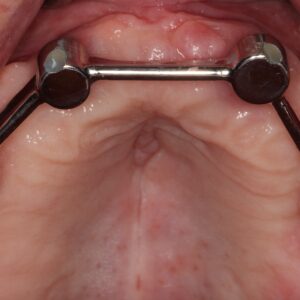

- Bar-retained dentures — A thin metal bar that follows the curve of your jaw is attached to the implants that have been placed in your jawbone. Clips or other types of attachments are fitted to the bar, the denture or both. The denture fits over the bar and is securely clipped into place by the attachment

Lower Jaw Bar Implant Overdentures